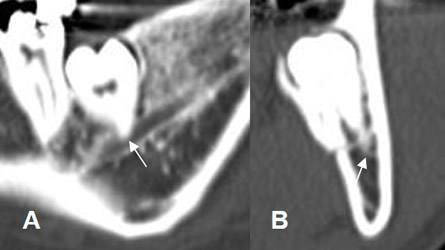

Fig 19. Patología asociada.

A: Dentascan reconstrucción coronal. Pérdida de piezas en ambas arcadas maxilares. Se aprecia engrosamiento en la mucosa de ambos senos maxilares, por sinusopatía, que debe ser tratada antes de colocar el implante.

B: TAC reconstrucción transversal. Sinusopatía maxilar, asociada a gran atrofia ósea.